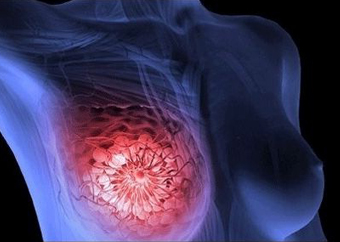

La criocirugía en cáncer de mama se realiza mediante la punción de una finísima criosonda mediante control de ultrasonido que permite la destrucción de forma segura e indolora del tumor, con magníficos resultados terapéuticos y estéticos. Es un proceso de carácter ambulatorio.

La terapia crioquirúrgica de cáncer de mama es posible llevarla a cabo con resultados interesantes pero siempre en casos muy seleccionados, estudios controlados y aprobados por los órganos de control (Ministerio de Salud, Comité Ético de Salud y la Organización Médica Colegial y Hospitalaria).